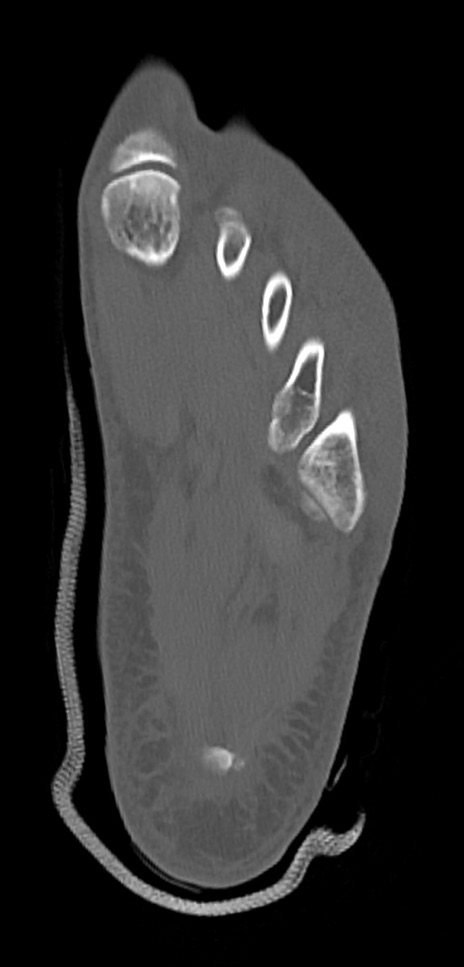

症例37 左足関節CT(横断像)

左足関節CT